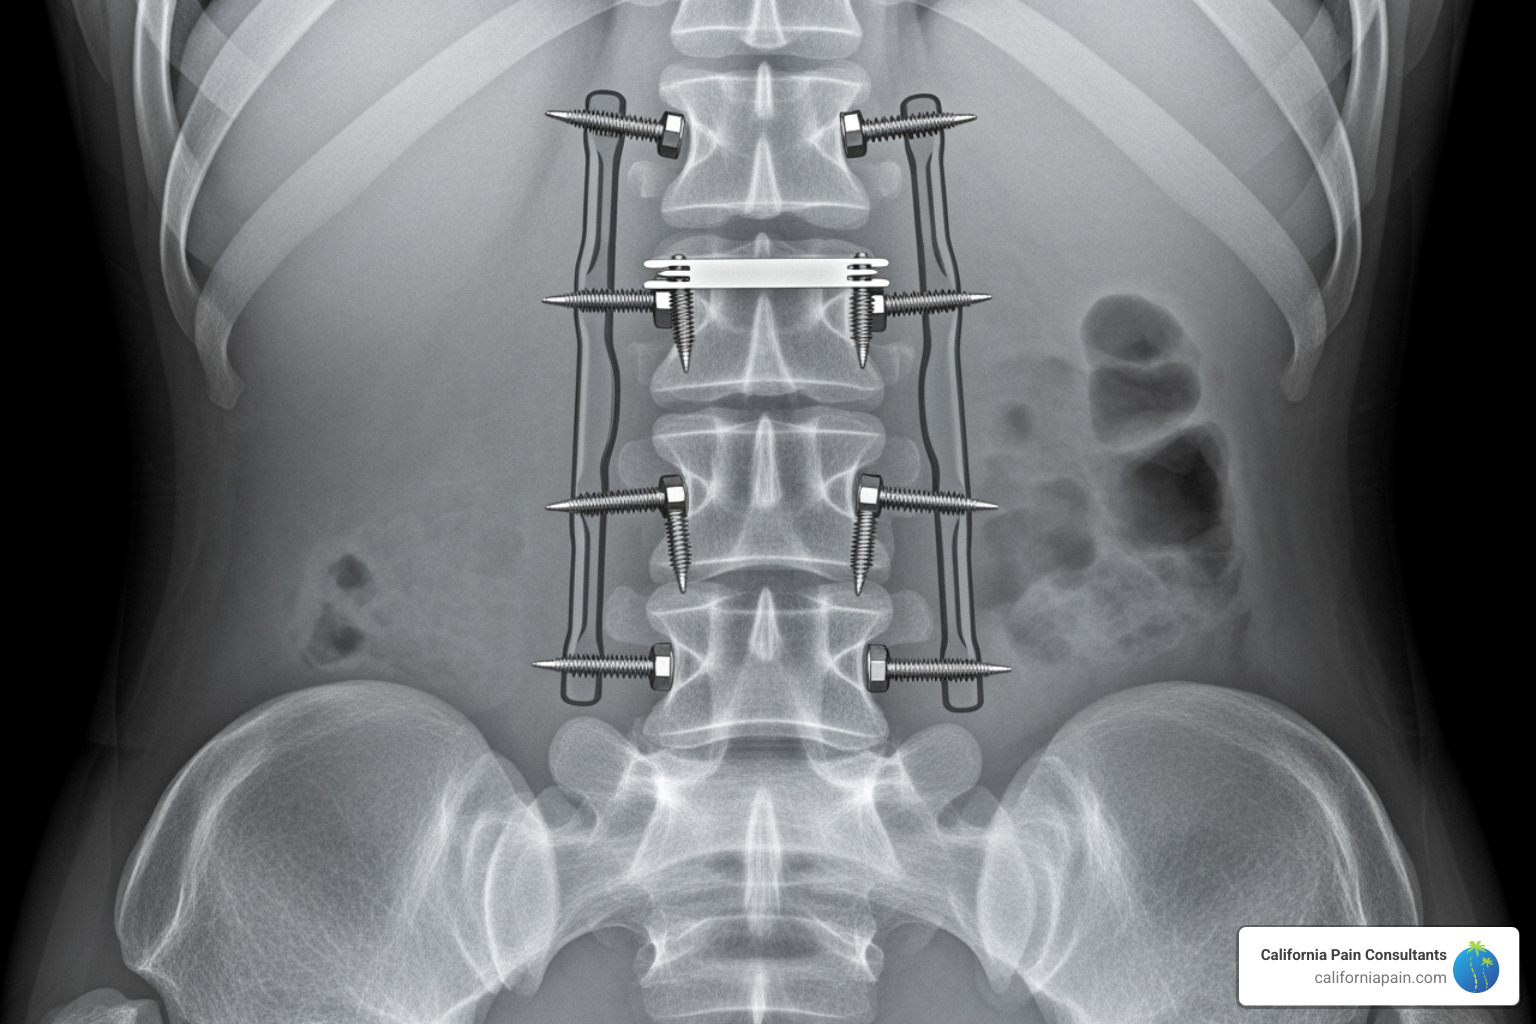

Structural and Hardware-Related Issues

Spinal fusion surgery aims to create a solid, stable bone segment. If the bones don’t fuse completely (a condition called pseudoarthrosis or “false joint”), the movement can cause pain. Factors that hinder fusion include smoking, excessive motion too early in recovery, and certain pain medications like NSAIDs.

Surgical hardware—screws, rods, and plates—can also become a source of back pain after spine surgery if they loosen, break, or irritate surrounding tissues. If the fusion has healed but the hardware is causing problems, removal might be an option to discuss with your specialist.